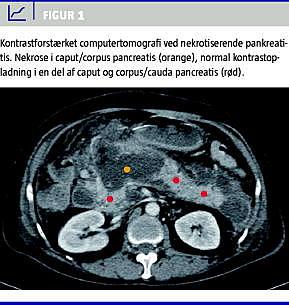

Morfologisk klassifikation

Den morfologiske beskrivelse af sygdommen AP baseres primært på fund gjort ved kontrastforstærket (contrast enhanced ) computertomografi (CECT) [16] (Figur 1 ). Herved kan der defineres tre specifikke sygdomstyper: 1) interstitiel, ødematøs pankreatitis (IEP), 2) nekrotiserende pankreatitis (NP) med nekrose af pankreasparenkymet (samt ofte tillige de peripankreatiske væv) og 3) NP med nekrose af udelukkende de peripankreatiske væv. Atlantaklassifikationen beskrev kun de første to sygdomstyper, hvorimod den isolerede peripankreatiske fedtnekrose, som ses hos op til 20% af patienter med svær AP, ikke blev omtalt som en selvstændig sygdomsenhed. Prognosen for sidstnævnte er generelt bedre end for patienter med intrapankreatiske nekroser [17], men udbredte peripankreatiske nekroser kan, specielt ved komplicerende infektion, også være livstruende.

Inddeles efter: 1) hvorvidt der er nekroser i selve pankreas eller alene de peripankreatiske væv, og 2) om nekroserne er inficerede eller ej. Diagnosen NP stilles ved manglende opladning i pankreas ved CECT. Nekrosens omfang har traditionelt været inddelt efter, om < 30%, 30-50% eller > 50% af pankreasparenkymet er involveret [18], hvilket opretholdes i den nye klassifikation. Ved mindre end 30% involvering bliver diagnosen usikker, og en opfølgende CECT (eller magnetisk resonans (MR)-skanning) efter minimum en uge kan være nødvendig. Diagnosen peripankreatisk nekrose stilles ved påvisning af en peripankreatisk ansamling med indhold af nekrotisk debris (se nedenfor, akut postnekrotisk ansamling).